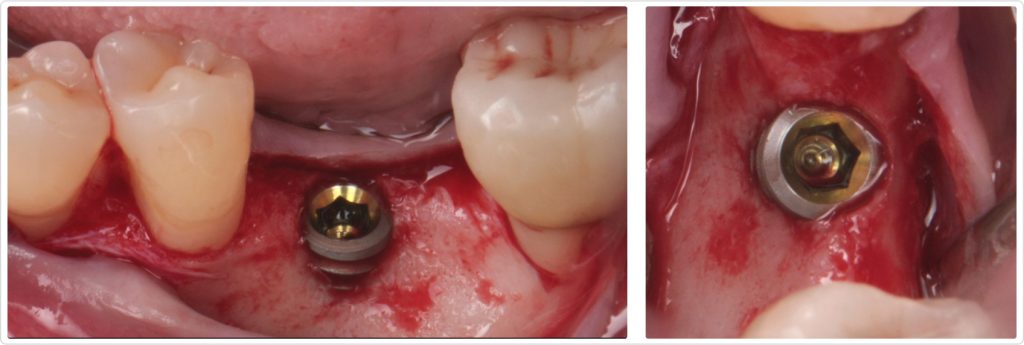

Implant placement and ridge augmentation

The implant (4.6 by 7.5 mm) was placed in an ideal 3D position with an equal distance to the adjacent teeth, 1 mm subcrestal and centered buccolingual (Figs. 4a and 4b). However, because of the significant ridge resorption, approximately 4 mm of the buccal rough surface of the implant was exposed, resulting in a bone dehiscence.

To address this, a cross-linked collagen membrane was used to cover the exposed implant, and a particulate bone graft using freeze-dried bone allograft (FDBA) was applied (Fig. 5). The collagen membrane was secured with resorbable 5-0 sutures anchored to the periosteum, ensuring stability of the graft material and facilitating bone regeneration. This suture stabilized the graft and relieved any extensive flap tension that could have compromised primary wound healing.